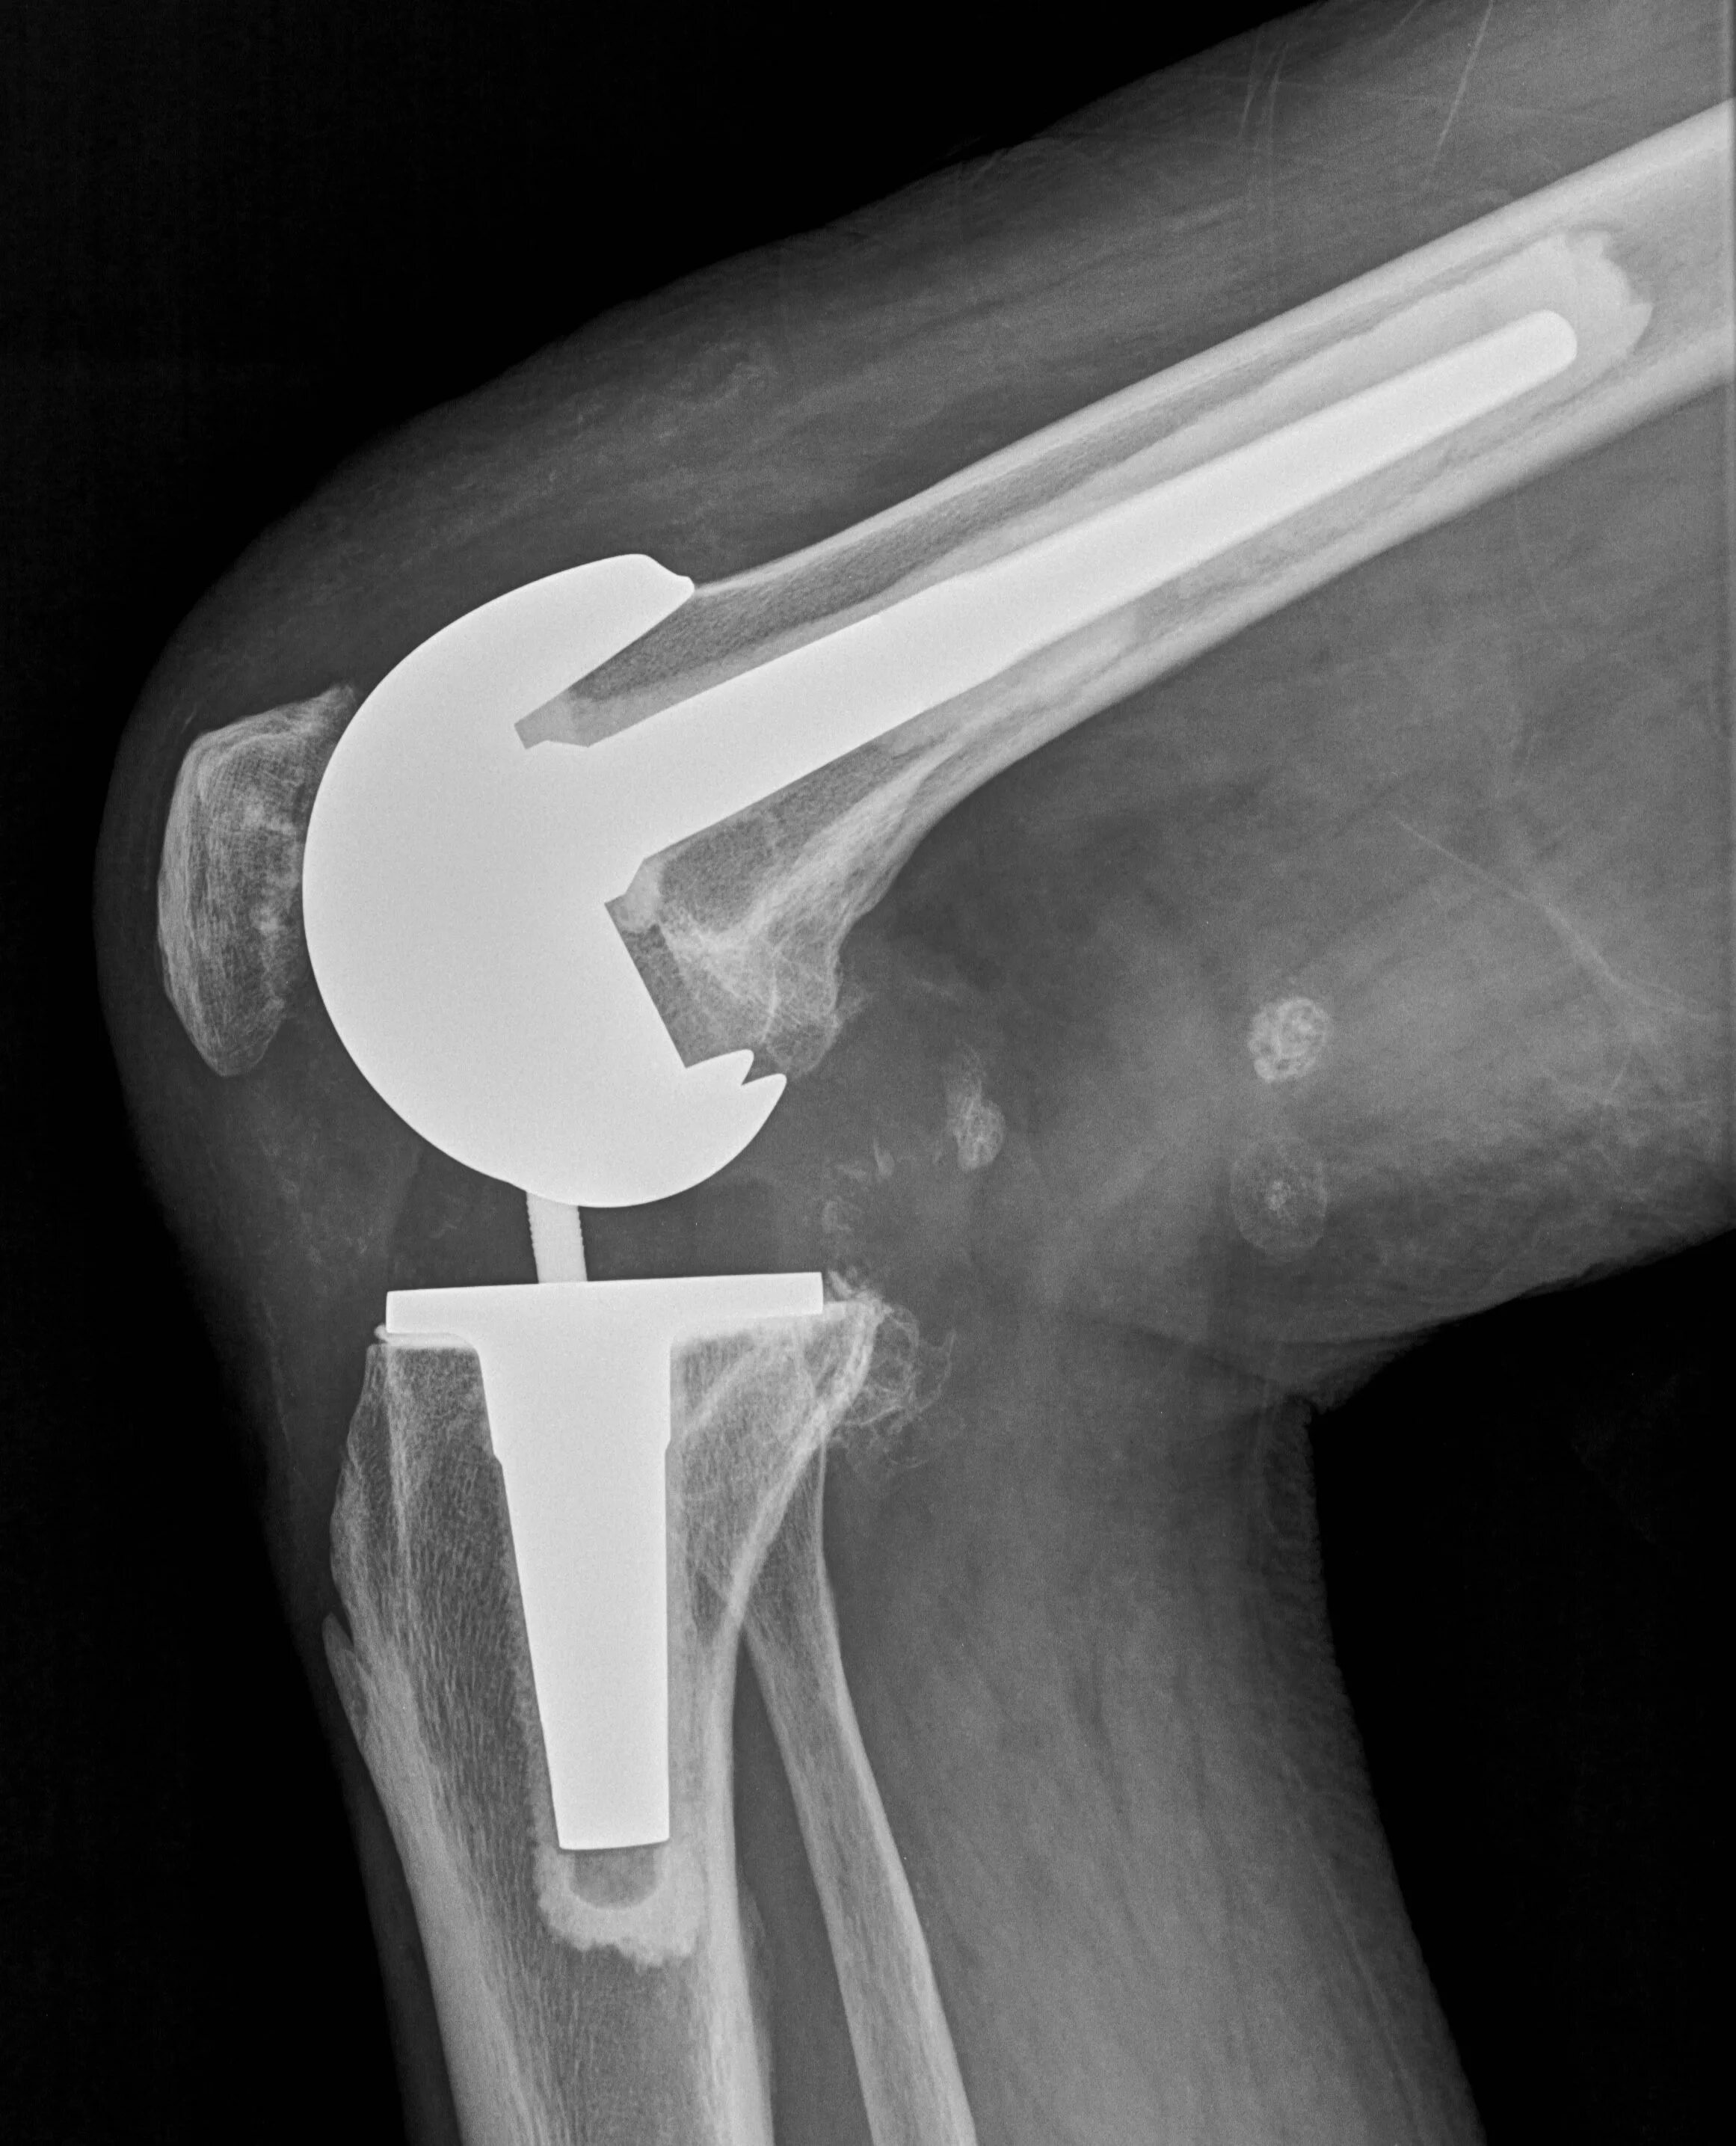

Эндопротез сустава мкб 10